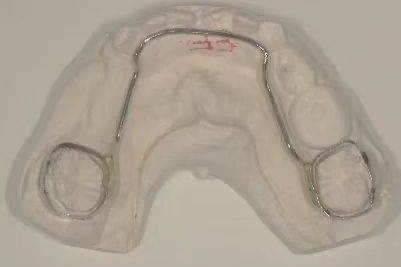

乳牙作为儿童的咀嚼器官,具有咀嚼、发音、美观及维持牙弓长度,促进颌面部正常发育的作用;同时乳牙作为天然的间隙保持器,可以很好地诱导恒牙的正常萌出。而临床由于严重的龋病、牙髓根尖周疾病及外伤等原因会导致乳牙过早丧失。乳牙过早缺失,将可能影响继承恒牙的正常萌出而造成恒牙排列不齐。乳前牙早失还会导致发音障碍,并且影响美观,甚至引起儿童心理问题。乳尖牙或乳磨牙早失后,发生恒牙列错畸形的机会比无乳牙早失者高3~4倍。 儿童牙齿早失后,为防止邻牙向缺隙部位倾斜和对颌牙伸长,可设计间隙保持器保持早失牙齿的近远中间隙和垂直间隙,促进继承恒牙正常萌出。 间隙保持器的种类 间隙保持器是通过维持早失牙间隙以保障牙弓长度的一种口腔装置,能在不影响患儿正常生长发育的同时,为正常咬合关系的建立提供有利条件。间隙保持器应在拔牙后几周内戴入,间隙丧失通常发生在乳磨牙过早脱落的6个月内。 带环或全冠丝圈式间隙保持器 主要适用于单侧单颗乳磨牙早失的治疗。 舌弓式间隙保持器 Nance弓(腭弓)式间隙保持器,主要适用于单侧或双侧多颗乳牙早失的治疗。 可摘式间隙保持器 主要适用于单颗或多颗乳牙早失的治疗,在保持间隙的同时,还能恢复部分咀嚼功能。 远中导板式间隙保持器 适用于第二乳磨牙早失、第一恒磨牙尚未萌出或萌出中。 间隙保持器注意事项 1. 保持器粘结后2小时内不能进食,待粘结材料完全固定后方可正常使用; 2. 保持良好的口腔卫生习惯,用牙刷和牙线清除牙菌斑和食物残渣; 3. 避免咀嚼硬而黏的食物; 4. 避免用舌头抵制保持器; 5. 前期1~3个月复诊,后期3~6个月复诊,直至恒牙萌出; 6. 若保持器松动移位或破裂,及时复诊。 佩戴间隙保持器后常见问题及解答 Q 间隙保持器佩戴后会不舒服吗? A 刚戴上间隙保持器会有几天的不适感,唾液增多和吐字不清也是正常的,佩戴后小朋友能很快适应。 Q 间隙保持器要佩戴多久? A 建议长期佩戴,直到替换恒牙长出来,具体时间根据个人实际口腔情况决定。 Q 间隙保持器会引起蛀牙吗? A 正确使用和维护间隙保持器,每天至少刷两次牙,配合使用牙线等清洁工具,并定期进行口腔检查。 Q 间隙保持器需要更换吗? A 在佩戴间隙保持器期间,牙齿可能会出现一些微小的移动,定期复查对于后期的佩戴效果十分关键,建议定期复查,如果出现佩戴不适、脱落等情况,建议及时检查,必要时重新制作间隙保持器。 Q 间隙保持器何时可以摘掉? A 家长可通过观察间隙保持器中间是否有白色牙尖萌出进行判断。